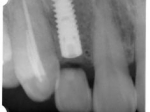

片側2歯欠損片側2歯欠損片側2歯欠損 主訴-入れ歯を使ってみたが違和感強くてダメ。固定のものにしたい。術前下顎口腔内(鏡像) 二次オペ時(鏡像)二次オペ時(鏡像)二次オペ時(鏡像) 術後術後術後、左下奥2本インプラント(鏡像) 術後(レントゲン)術後(レントゲン)術後(レントゲン)、左下奥2本インプラント